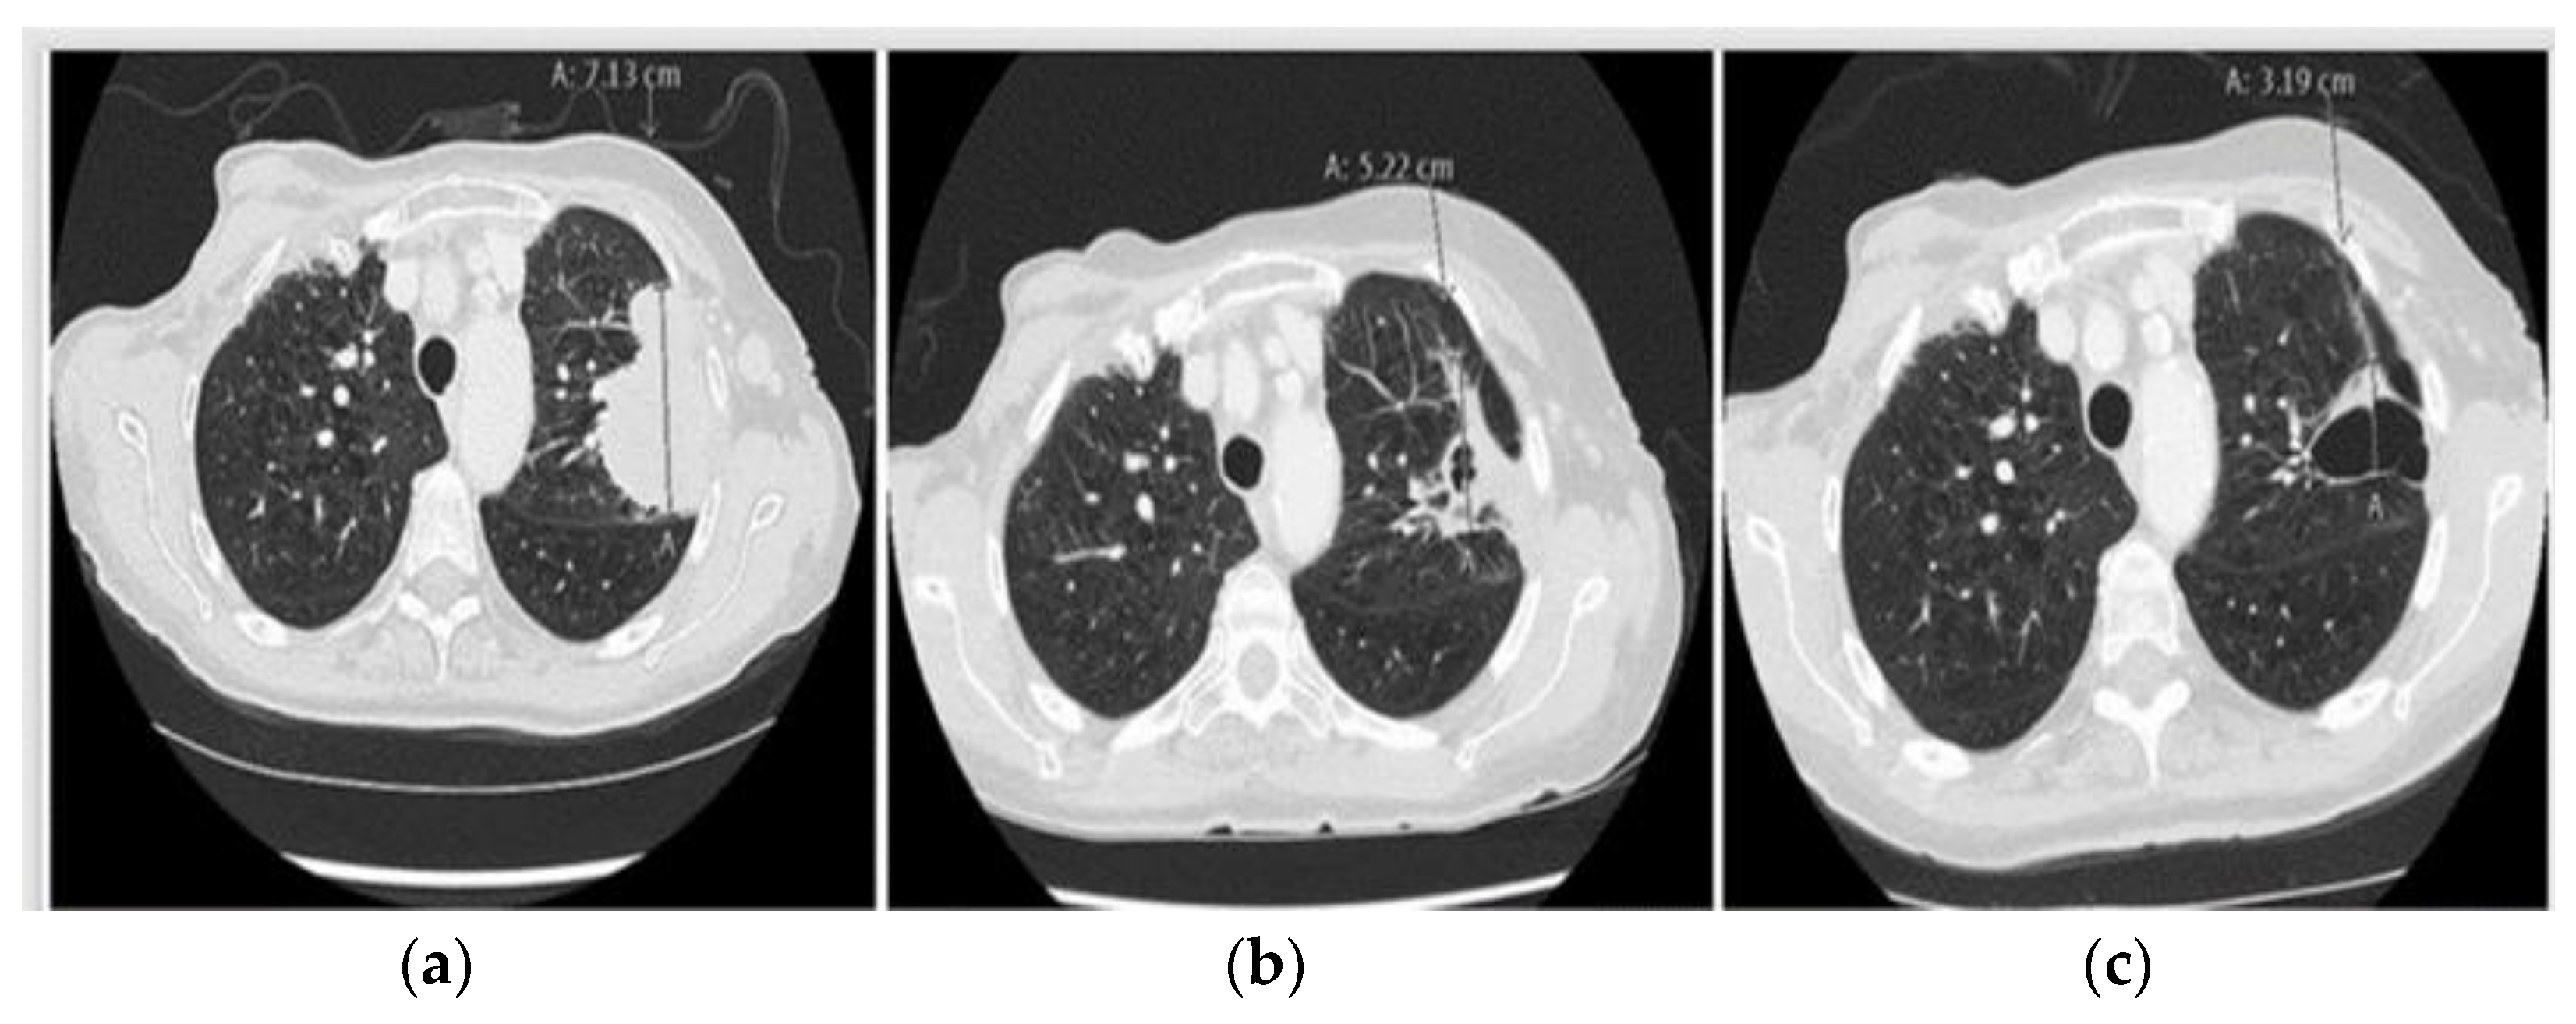

2.1. Case 1: Metastatic NSCLC with EGFR ex19del and Acquired MET Amplification: Short-Term Complete Response (CR) by Combining Crizotinib with Osimertinib